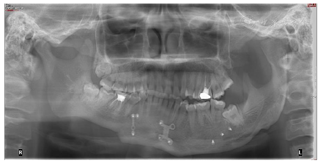

曲面体层片检查(图3):左侧髁突膨大,下颌体部及颏部可见钛板钛钉影像。

。曲面体层片检查:左侧髁突膨大,下颌可见钛板及假体。头颅正、侧位片检查:骨性Ⅰ类伴面部不对称畸形。CBCT检查:左侧髁突膨大,表层骨皮质连续。放射性核素检查:双侧髁突骨盐代谢比右:左=1:1.76。

26大面积银汞充填体,46牙色充填体。

32-43对应前庭沟处黏膜可见瘢痕。